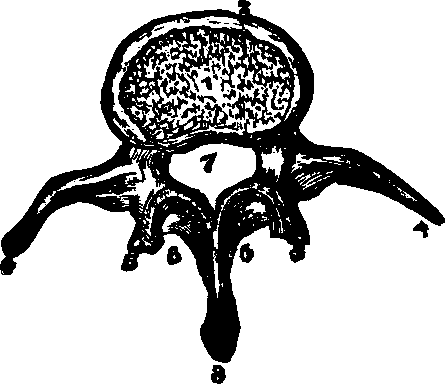

Fig. 14. Backbone, spinal

column, or vertebral column. All animals possessing such a row of bones are

called vertebrates. Above b are the cervical (neck)

vertebræ; b to c, dorsal (back) or chest

vertebræ; c to d, lumbar (loins) vertebræ;

d to e, sacrum; e to f, coccyx.

The Spinal Column or backbone, when viewed from the front presents a perpendicular appearance, but a side view shows four distinct curves. The bones composing it are called vertebræ. The body part of a vertebra is light and spongy in texture, having seven projections called processes, four of which are the articular processes, which furnish surfaces to join the different vertebræ of the spinal column. Two are called transverse, and the remaining one is termed the spinous. The transverse [pg 25]and spinous processes serve for the attachment of the muscles belonging to the back. All these processes are more compact than the body of the vertebra, and, when naturally connected, are so arranged as to form a tube which contains the medulla spinalis, or spinal cord. Between the vertebræ is a highly-elastic, cartilaginous and cushion-like substance, which freely admits of motion, and allows the spine to bend as occasion requires. The natural curvatures of the spinal column diminish the shock produced by falling, running or leaping, which would otherwise be more directly transmitted to the brain. The ribs at the sides, the sternum in front, and the twelve dorsal bones of the spinal column behind, bound the thoracic cavity, which contains the lungs, heart, and large blood-vessels.